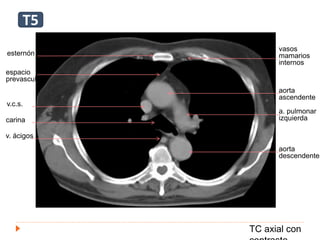

esternón

v.c.s.

carina

v. ácigos

espacio

prevascular

aorta

ascendente

a. pulmonar

izquierda

descendente

vasos

mamarios

internos

T5